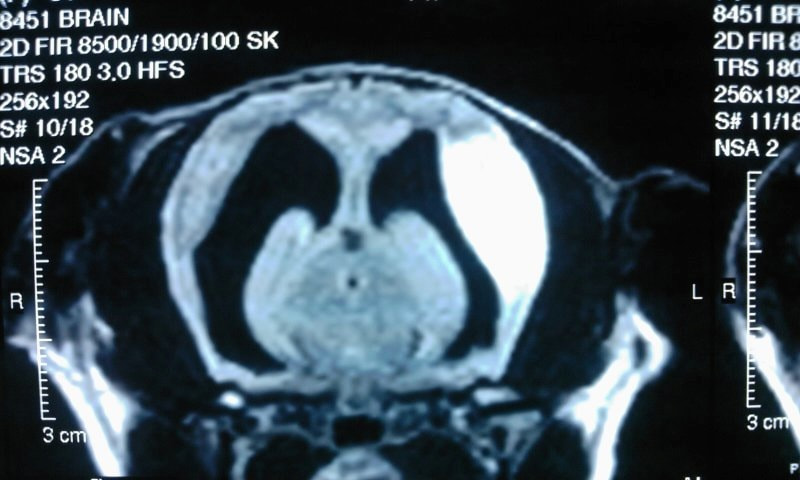

初発日から9ヶ月後、それまで落ち着いていた発作が相次いでみられた為、MRI撮影を行なった。MRIでは右前頭葉、側頭葉、頭頂葉、側頭葉の一部に壊死や線維化を疑う所見がみ られた。側脳室の重度拡大、脳萎縮がみられた。また、後頭骨の奇形、脊髄空洞症がみられた。脳脊髄液の細胞数は正常範囲内であり、坑GFAP抗体は陰性であった。

T1強調画像

T1強調画像(造影)